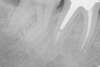

Le patient se présente suite à une douleur à la mastication, l'examen clinique révèle un abcès en regard des racines de la molaire et la radiographie objective deux infections à l’extrémité des racines ainsi qu'un traitement canalaire insuffisant (photo 1). La couronne céramique et l'inlay core sont déposés puis un retraitement canalaire est entrepris pour désinfecter et obturer complètement les racines (photo 2). Une reconstitution de la dent à l'aide d'un inlay core et d'une couronne céramo-métallique est réalisée pour conserver l’étanchéité et la pérennité du retraitement.Radiographie à 3 ans objectivant la disparition complète de l'infection, la dent est saine et asymptomatique (photo 3)